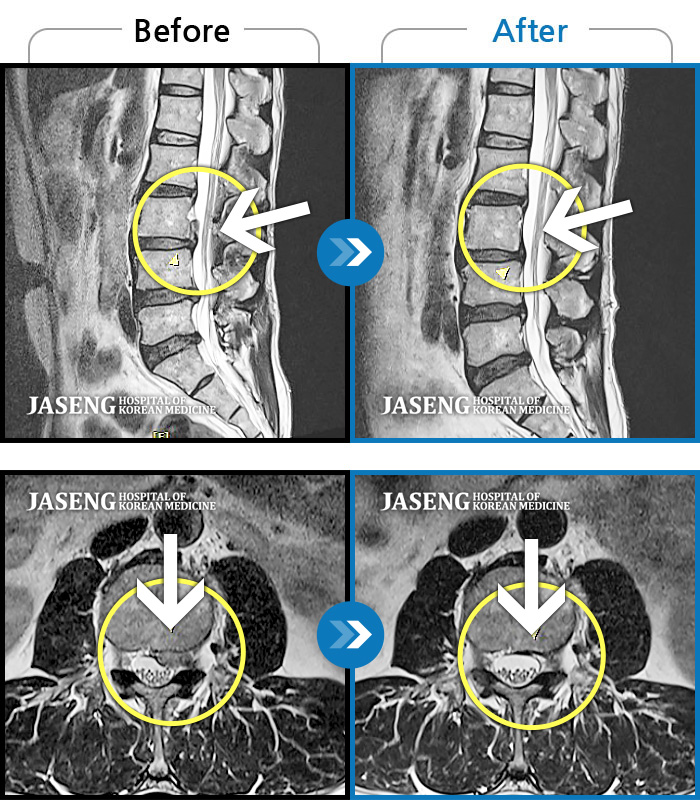

Before

After

환자에게 사전 동의를 받아 동일 조건에서 촬영되었습니다.

개인에 따라 치료 후 부작용이 발생할 수 있으니 의료진과 상담 후 치료를 진행하시기 바랍니다.

허리와 양 다리의 타는 통증으로 걷지 못한 상태로 내원

짐을 들면서 정리하다가 디스크가 터져서 내원, 후에 통증이 더 심해져 내원